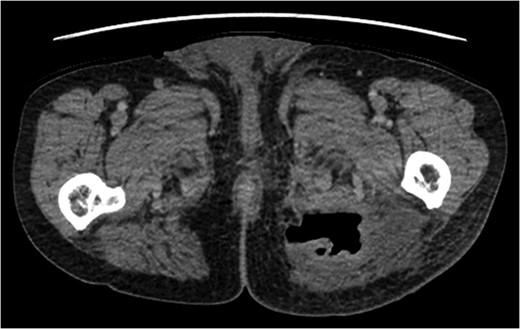

A rare complication of diverticular disease is the formation of fistulas, most commonly either colo-vesical or colo-vaginal. We present the unusual case of a perforated sigmoid diverticulum forming a colo-gluteal fistula and presenting initially as a gluteal abscess in an otherwise asymptomatic patient. After drainage of the gluteal abscess, the patient re-presented with faecal loss from the abscess drainage site. Imaging revealed fistulous communication between the sigmoid and the left obturator internus muscle, tracking to the gluteus maximus with associated abscess and cutaneous communication to the site of previous drainage. The patient underwent an emergency Hartmann's procedure with lay open/abscess drainage of the gluteal cavity. Post-operatively the patient experienced continuing discharge from the gluteal fistula despite repeated drainage and debridement causing considerable morbidity, inconvenience and misery. Clinicians should maintain a high index of suspicion when presented with a gluteal abscess and should consider the possibility of an intra-abdominal source.

The patient re-presented a week after discharge, complaining off persistent pain around the buttock, with feculent discharge and flatulence from the wound. Abscess cultures from the previous admission were reviewed and noted to have grown Escherichia coli and clostridium species.

An emergency Hartmann's procedure was performed under general anaesthetic through a lower midline incision as well as lay open of the perineal fistula. On opening the abdomen, a perforated diverticulum was identified extending into the left lateral pelvic wall. A standard Hartmann's procedure was performed, with sigmoid colectomy, division of rectum at recto-sigmoid junction and a tension-free stoma formed in left hypochondrium. The left buttock abscess cavity extended by a further 2–3 in. and the cavity then packed.

The culture results in this case showing the presence of E. coli and clostridium species, along with flatulence and feculent discharge from the wound pointed towards a fistulous communication with the gastro-intestinal tract. These pointers were, however, realised after the patient had suffered considerable distress with symptoms and delay in diagnosis.